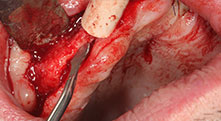

¿Podría describirnos brevemente cómo procede, por ejemplo, a la hora de mover injertos óseos destinados a trasplantes?

Bratu: Preferimos realizar las osteotomías en la línea oblicua externa de la cara posterior del maxilar inferior, y no en la región situada entre los orificios. Tras realizar una incisión en los tejidos blandos, utilizamos las nuevas sierras para definir el contorno de la osteotomía. De este modo, conseguimos una preparación completa en prácticamente el 80 por ciento de los casos. Por otro lado, en algunas ocasiones también utilizamos otros insertos piezoquirúrgicos, así como un cincel para mover el injerto. Para nosotros, esta es una técnica de intervención muy eficaz.